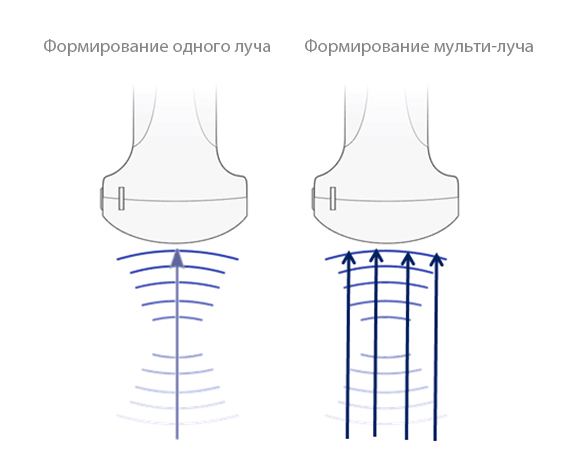

Формирование мульти-луча

Увеличивает скорость обработки луча в 12 раз.